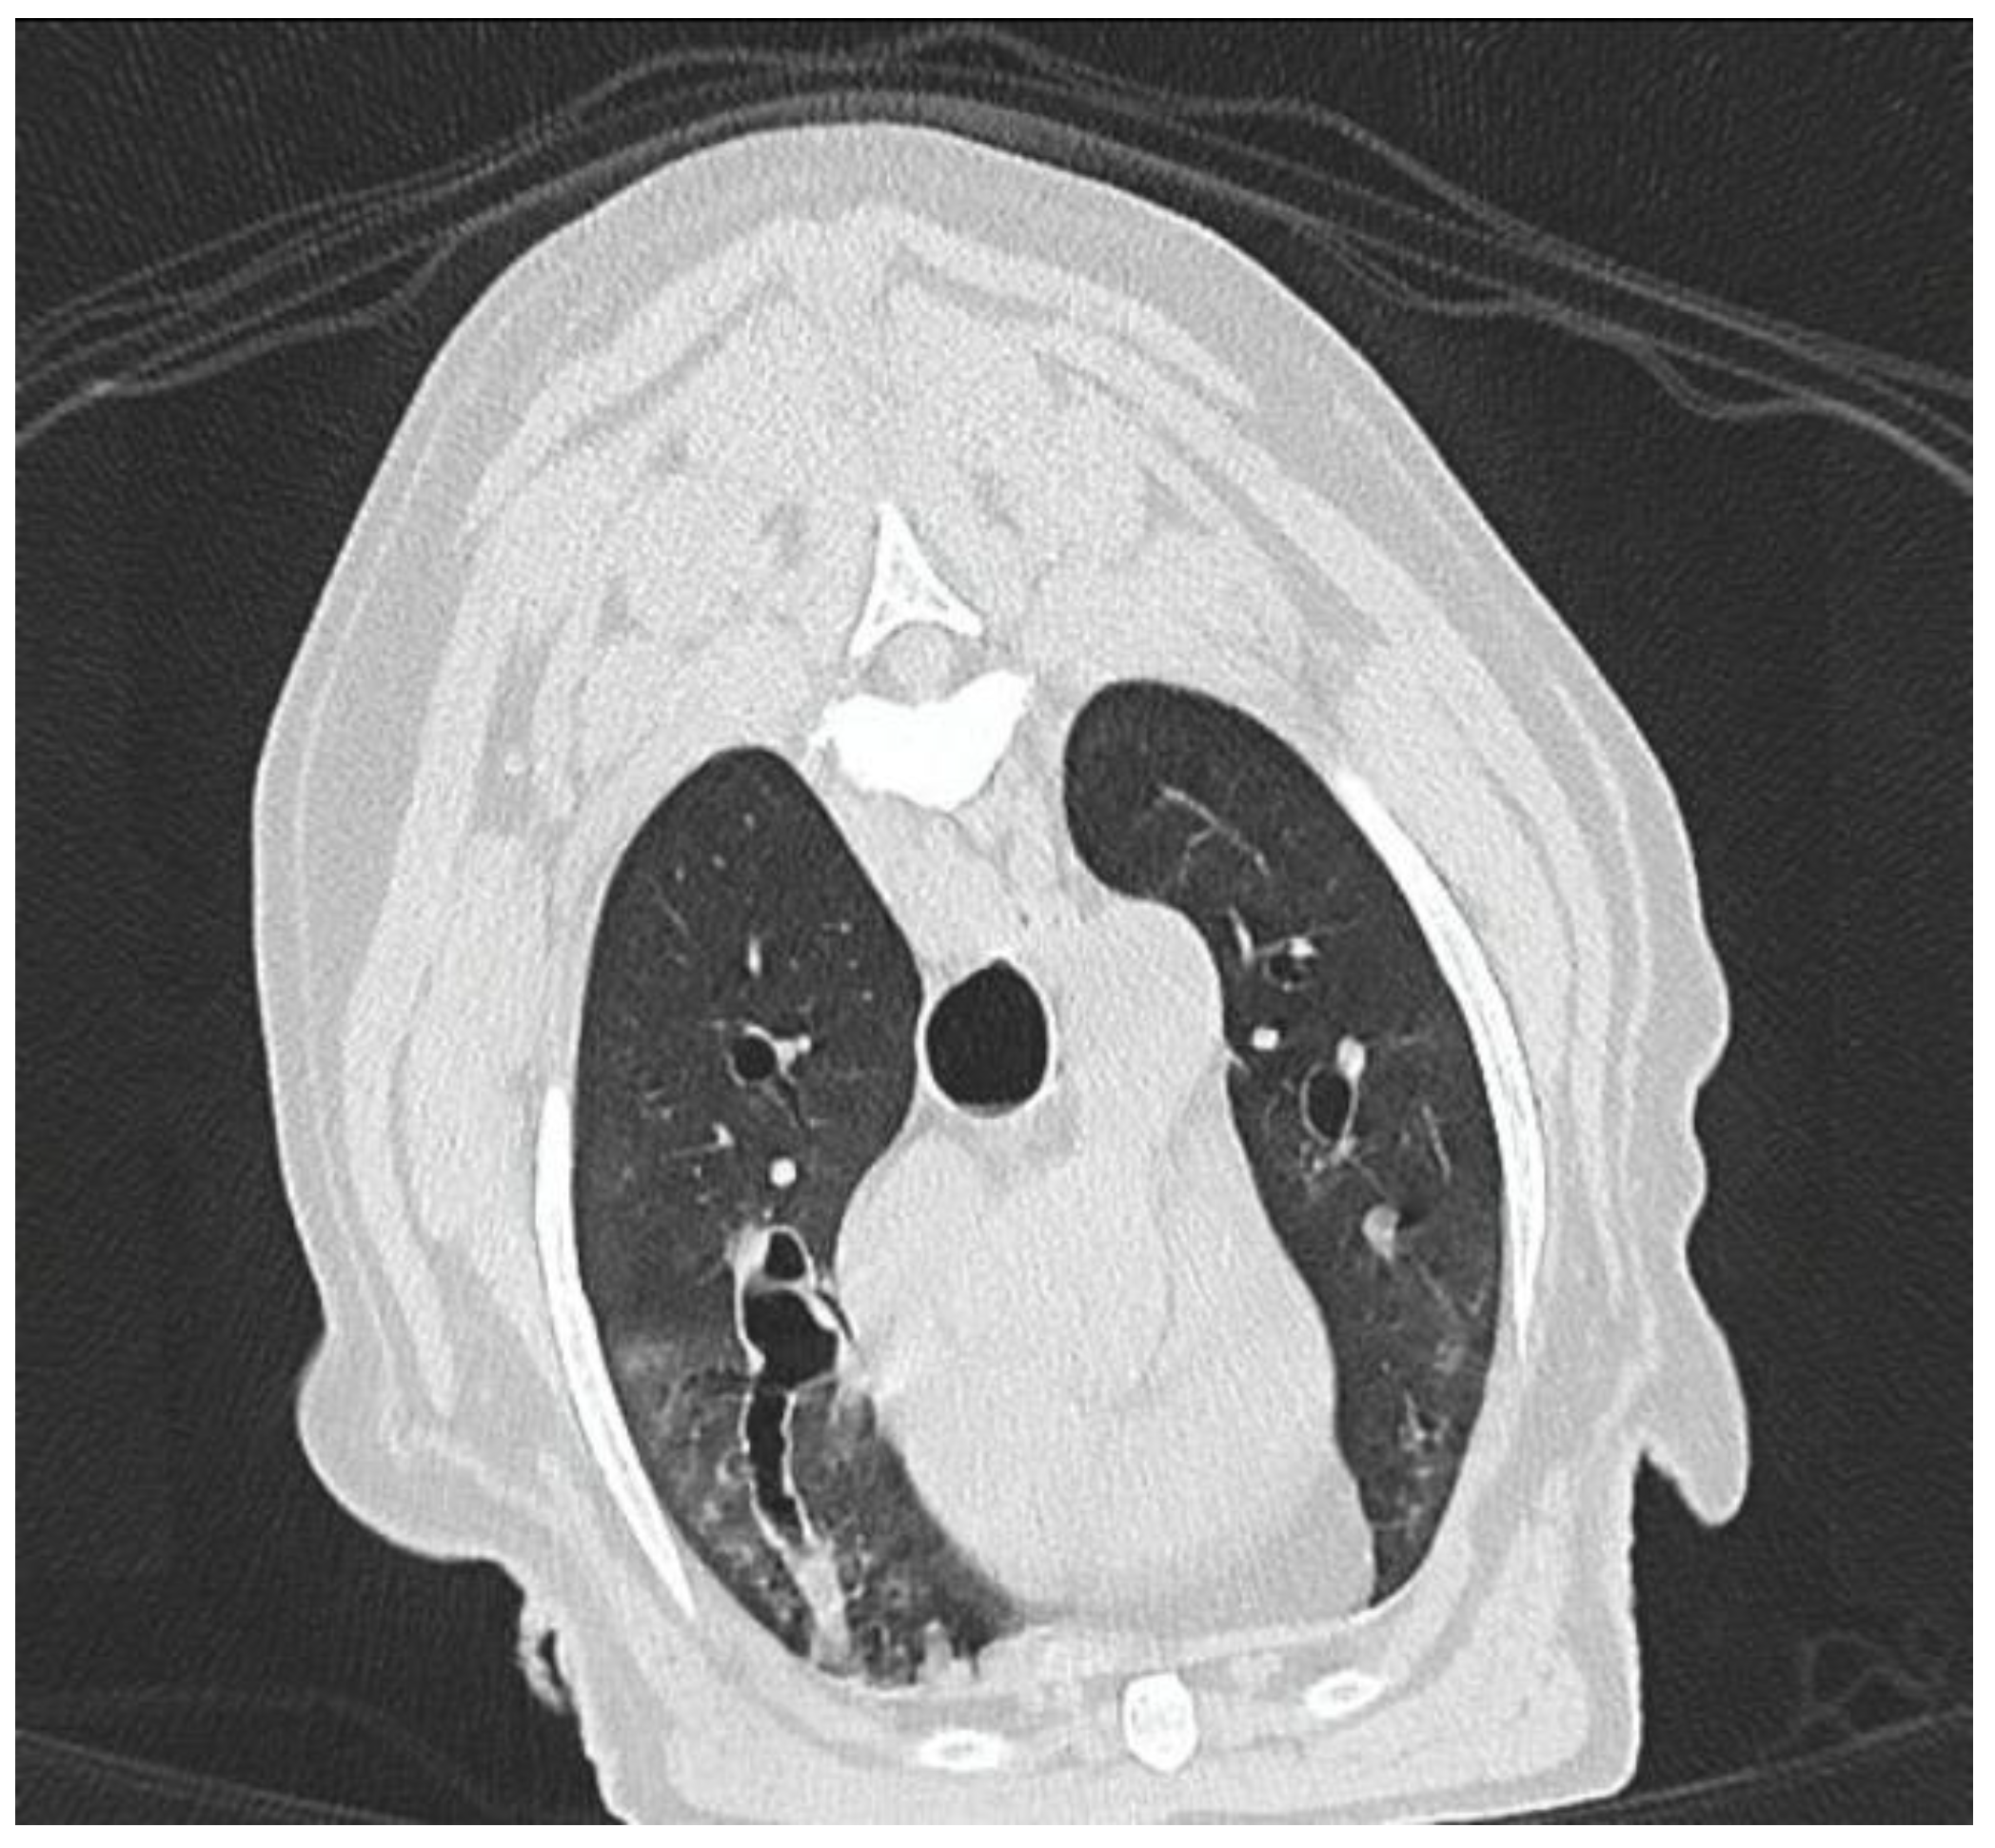

3.1.8. Computed Tomography Findings

3.2.2. Thoracic CT Versus Endoscopy